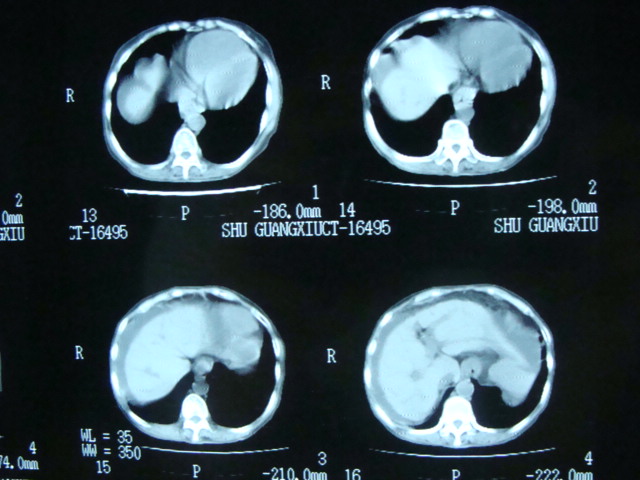

标题: CT13799:风心?肺动脉发育异常?

xxx女.72岁,胸闷不适,一侧下肢水肿.肺窗没见异常.不上传.

肺动脉根部,右室增宽;肺门小;是什麽征象///

右肺动肺截断.肺动肺脉高压

我看食管下段管腔狭窄,壁明显厚,腹水,肝右叶低密度灶

食管癌?肝转移?腹水

主肺动脉扩张,腹水.

考虑:1、肺动脉高压(原因?);

2、肝硬化伴腹水。